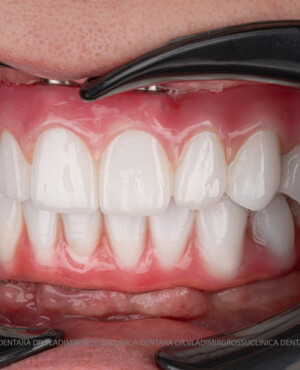

Caz 1

Caz 2